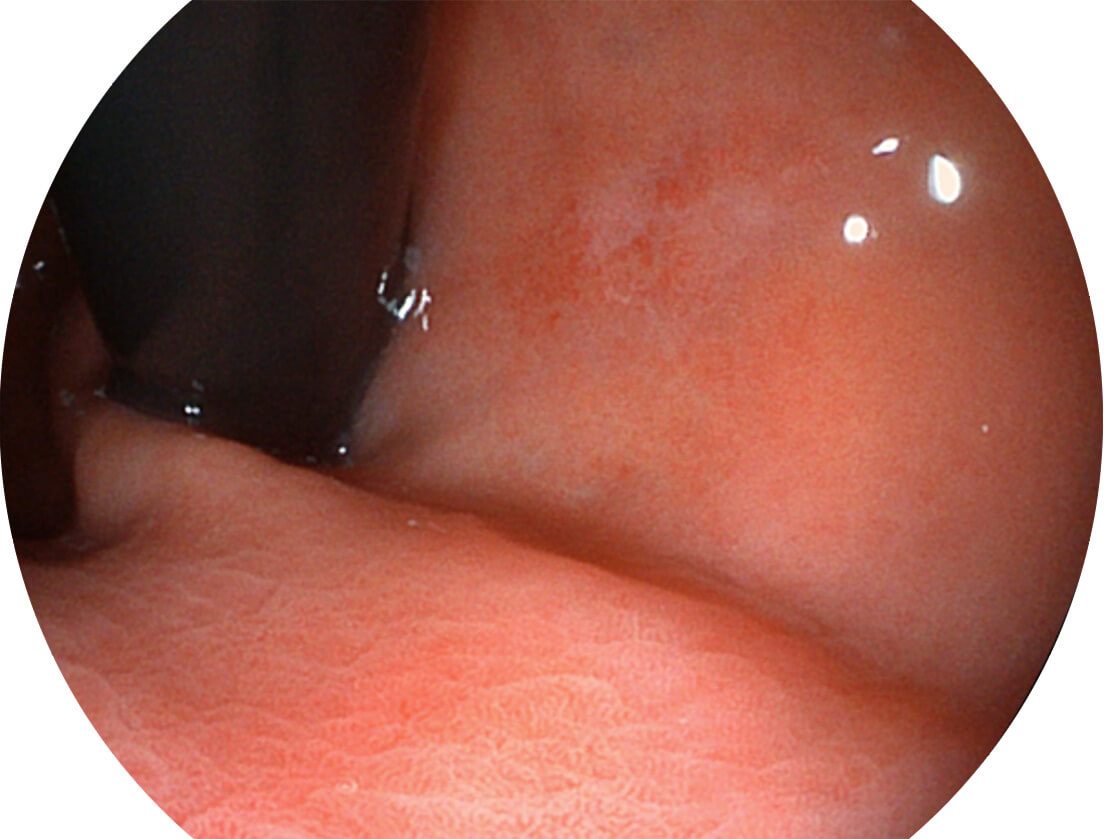

白光图像

VIST图像

Versatile Intelligent Staining Technology, VIST

强调浅层黏膜结构的同时,保证照明亮度和提升浅层微血管与中层血管颜色对比度,病变边界更清晰。